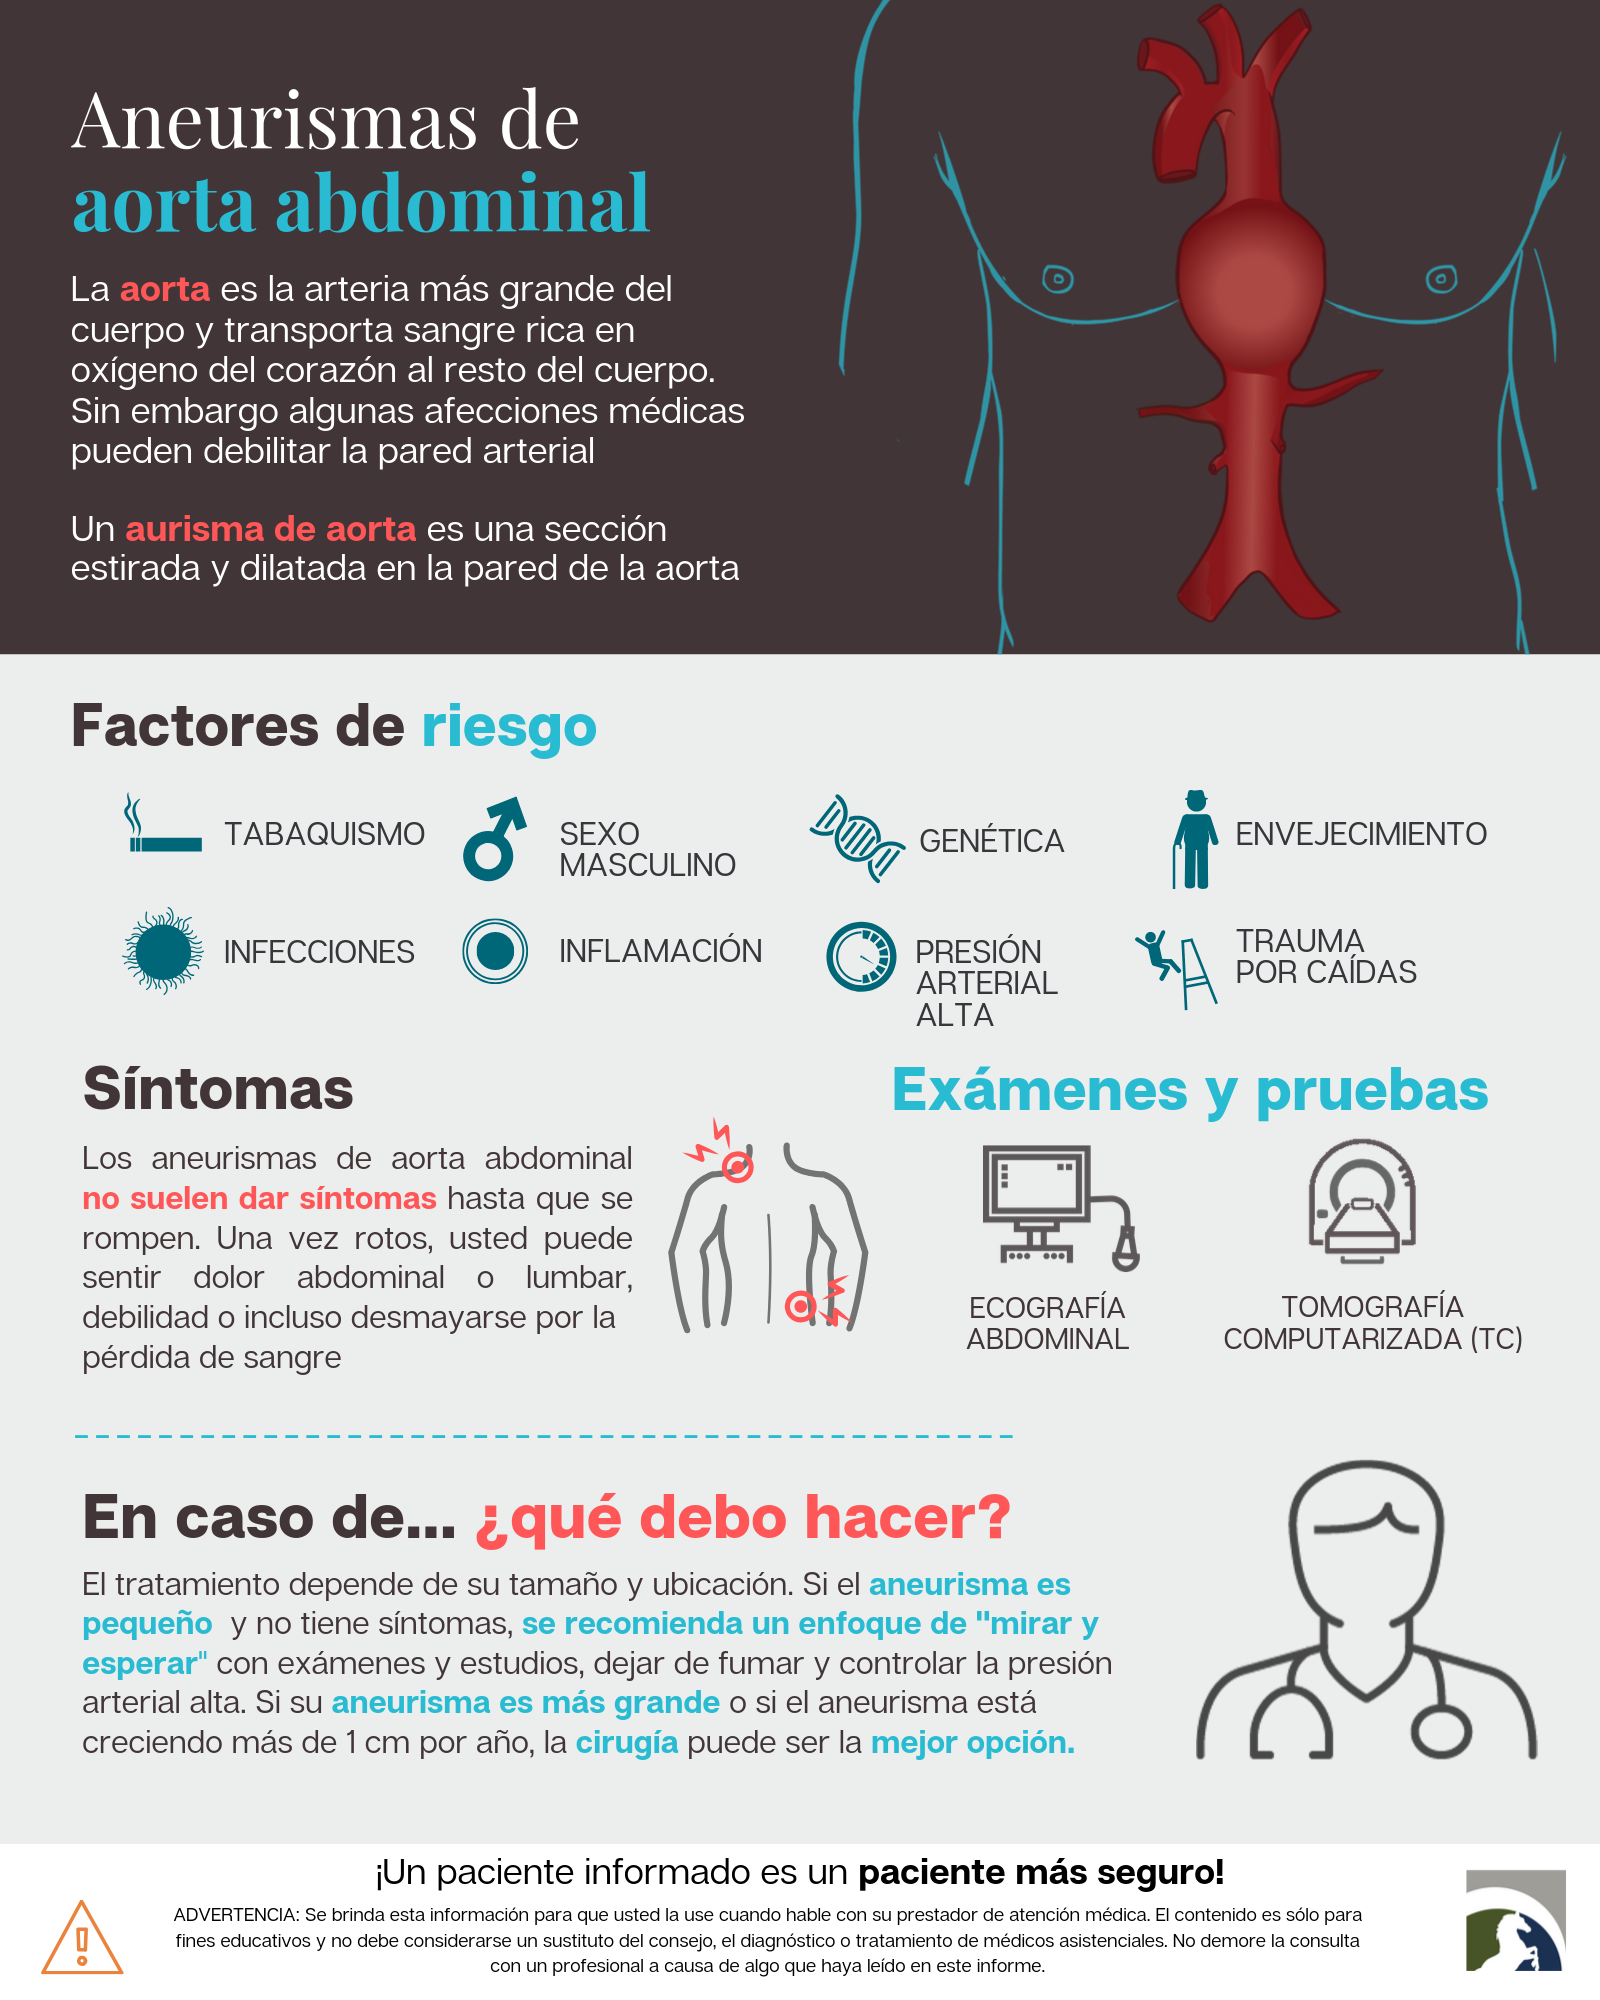

Un aneurisma aórtico abdominal es un agrandamiento de la parte baja de la aorta que se extiende a.

aneurisma de la aorta abdominal La aorta va desde el corazón hasta el. Recibe sangre con gran contenido en oxígeno. Cirugía vascularrupturas de aneurisma de la aorta abdominal: La cirugía de reparación abierta de aneurisma aórtico abdominal (aaa) se realiza para arreglar una parte dilatada de la aorta. Si tienes un aneurisma de la aorta abdominal en expansión, podrías notar lo siguiente: La incidencia de aaai en. En este artículo examen físico pruebas de detección y de diagnóstico ¿quiénes deben someterse a un examen de detección de aneurisma de aorta torácica? Los aneurismas aórticos aneurismas aórticos la aorta, que mide alrededor de 2,5 cm de calibre o diámetro, es la arteria más grande del cuerpo.